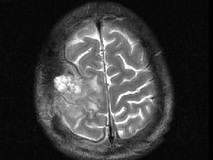

男,63岁,反复抽搐30余年加重伴左侧肢体活动不利活1月余,PE:右顶部约4cm×5cm大小隆起包块质硬,不能活动,右上下肢肌力Ⅴ,左上下肢肌力Ⅳ+,根据所提供图像,最可能的诊断为()

A.右顶骨(付脊索瘤)或称为肌上皮瘤

B.右顶骨转移瘤

C.右顶骨骨瘤

D.右顶骨血管瘤

E.右顶骨胆脂瘤

[单选题]男,63岁,反复抽搐30余年加重伴左侧肢体活动不利活1月余,PE:右顶部约4cm×5cm大小隆起包块质硬,不能活动,右上下肢肌力Ⅴ,左上下肢肌力Ⅳ+,根据所提供图像,最可能的诊断为()A . 右顶骨(付脊索瘤)或称为肌上皮瘤B . 右顶骨转移瘤C . 右顶骨骨瘤D . 右顶骨血管瘤E . 右顶骨胆脂瘤